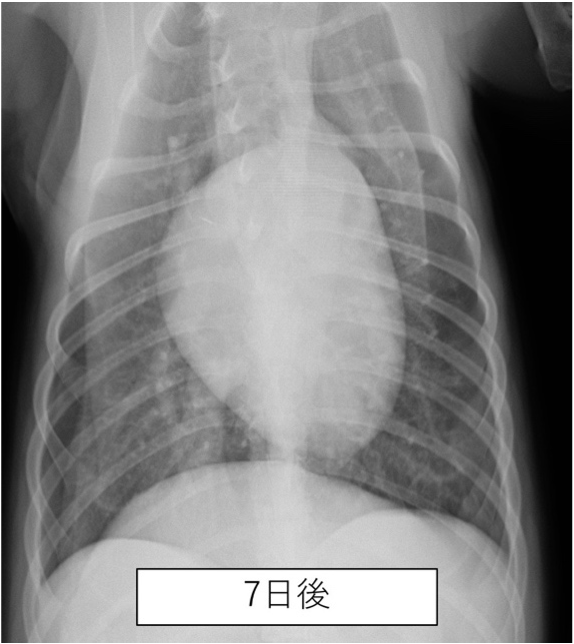

胸部のレントゲン撮影にて肺野全体の不透過性亢進(白く見える部分)が認められた。

| 誤嚥性肺炎とは、唾液や食べ物、胃液、吐物などの異物を吸引してしまうことで生じる肺炎です。加齢などにより気道反射が低下している動物や短頭種(パグやブルドッグなど)で起こりやすいと言われています。 本症例は上記の条件に当てはまりませんが、スポンジをかじる中で細かい粒子を吸い込んでしまった可能性があります。 幸いにも、本症例は抗生物質の投与により2週間ほどでレントゲン画像所見は消失し治療終了となりましたが、場合により致命的な状態まで悪化してしまうこともあります。早期発見・治療が重要です。 |